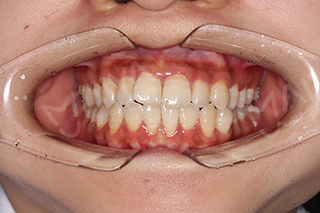

如今的华小雪已经成功矫正完成,再次对着镜子露出自信的微笑,“隐适美在不知不觉中就把我的牙齿矫正好了,真的太神奇了,非常感谢张超主任,感谢麦芽口腔!”